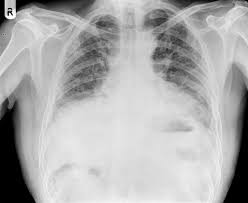

“폐에 물이 찼다”는 말을 들으면 대부분 같은 그림을 떠올리지만, 실제로는 두 가지가 섞여 불리는 경우가 많습니다. 하나는 폐 안(폐포)에 물이 스며드는 폐부종, 다른 하나는 폐 바깥(흉막 사이)에 물이 고이는 흉수(흉막삼출)예요. 둘 다 숨이 차지만, 동반 증상과 위험 신호가 조금 다릅니다. 오늘은 “폐에 물이 차는 증상”을 최대한 쉽게, 실제로 느끼는 증상 중심으로 정리해드릴게요.

폐부종(폐 안에 물)일 때 특징적인 신호

폐부종은 말 그대로 폐포 쪽으로 물이 스며들어 산소 교환이 어려워지는 상태라, 증상이 갑자기 세게 올 수 있습니다. 특히 아래 느낌이 있으면 “그냥 감기인가?”로 넘기기 어렵습니다.

폐부종은 심장 문제(심부전 등)와 함께 오는 경우가 흔해, 갑작스러운 호흡곤란에 가슴 답답함, 식은땀, 심장이 두근거림이 같이 오면 더 주의가 필요합니다.

흉수(폐 바깥에 물)일 때 흔한 느낌

흉수는 폐 바깥쪽 공간에 물이 차서 폐가 눌리는 형태라, 보통은 서서히 숨이 차는 쪽이 많습니다. 초기엔 “체력이 떨어졌나?” 정도로 시작했다가 점점 불편해지기도 해요.